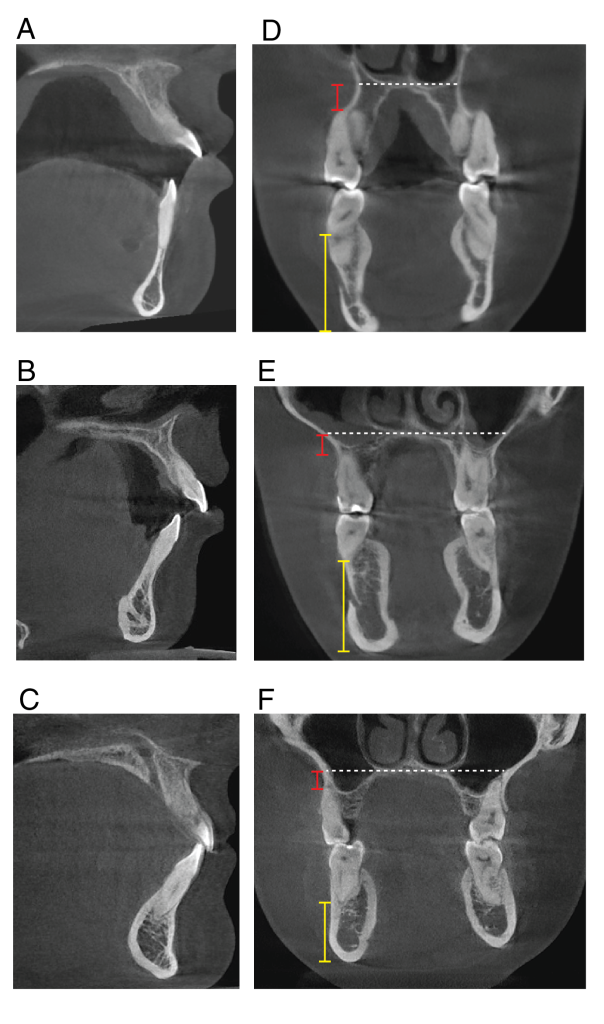

Figure 7: Zygomatic bone in NM patients. 3D CBCT reconstruction of the (A) NM patient, (B) matched open bite patient, and (C) matched control patient. The orbital rim, zygoma, and maxilla body demonstrate thinner cortical bone and more porosity.

Figure 8. Upper and lower alveolar bone, palate, and symphysis in an NM patient. Radiographic images of the NM patient (A, D), matched open bite (B, E), and matched control patients (C, F). The red bar demonstrates the distance between the palate and the apex of the first molar, while the yellow bar demonstrates the distance between the border of the mandible and the apex of the first molar.